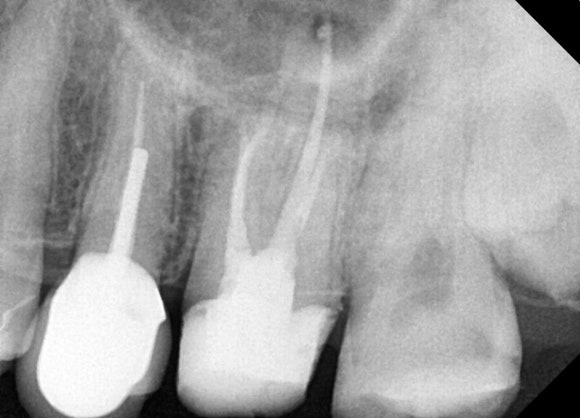

엑스레이를 노려보니

생각보다 뿌리의 길이가 깁니다.

잇몸도 건강하고 두꺼워보입니다.

그럴땐 치은절제술을 통해 뿌리의 일부를 노출시킵니다.

위 사진은 충치를 모두 제거하고 치은절제술로 뿌리를 노출시킨 사진입니다.